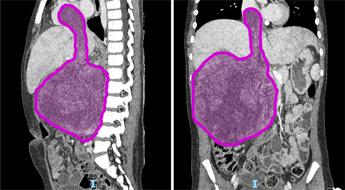

(Adnkronos) – Sei cicli di chemioterapia, poi nove ore di intervento ma ora il tumore di circa 1,5 chili di cui era affetta Sara (nome di fantasia), a soli otto anni, è stato rimosso. "Un intervento chirurgico complesso e straordinario", ha spiegato in una nota l'ospedale pediatrico Bambino Gesù di Roma dove è stata operata la bambina. "Questo successo non è solo una vittoria medica, ma anche una grande speranza per tante famiglie che affrontano situazioni simili", ha affermato Alessandro Crocoli, responsabile dell’Unità di Chirurgia Oncologica. "Sara (nome di fantasia), 8 anni appena compiuti, era affetta da un nefroblastoma al rene destro che si estendeva all’interno della vena renale, della vena cava inferiore fino a raggiungere l’atrio destro del cuore, a causa di una trombosi neoplastica. Questa rara estensione del tumore – ha spiegato l'ospedale – si verifica in appena il 4-10% dei casi di nefroblastoma. Prima dell’intervento Sara è stata sottoposta a sei cicli di chemioterapia, eseguiti dal team di oncologi guidati dal professor Franco Locatelli, per ridurre la massa tumorale e facilitare l’operazione. La fase preparatoria pre-chirurgica si è avvalsa di tecniche all’avanguardia di diagnostica per immagini come l’elaborazione 3D del tumore da asportare realizzata dall’unità di Imaging avanzato cardiotoracovascolare e fetale". "L’intervento, reso possibile dalla collaborazione tra oncologi, chirurghi, cardiochirurghi, e anestesisti, rappresenta un risultato importante per la medicina pediatrica", ha reso noto l'ospedale pediatrico Bambino Gesù. L’operazione ha avuto una prima fase in cui l’équipe di chirurgia oncologica, formata dal dottor Alessandro Crocoli e dalla dottoressa Chiara Grimaldi, ha rimosso il rene destro, "il cui volume era dieci volte superiore rispetto alla norma a causa del tumore. Successivamente i cardiochirurghi, guidati dal professor Lorenzo Galletti e con il dottor Gianluca Brancaccio come primo operatore, hanno temporaneamente arrestato il cuore della bambina, mantenendola in vita con la circolazione extracorporea, per rimuovere la parte del tumore che aveva invaso l’atrio destro – prosegue la nota dell'ospedale del Vaticano – Infine, dopo aver riavviato il cuore, i chirurghi hanno completato l’operazione rimuovendo il residuo tumorale dalla vena cava inferiore. In totale, il tumore asportato pesava circa 1,5 kg. La parte anestesiologica del complesso intervento, durato più di 9 ore, è stata gestita dal team della Terapia Intensiva Cardiochirurgica del dottor Luca Di Chiara". "Questo successo non è solo una vittoria medica, ma anche una grande speranza per tante famiglie che affrontano situazioni simili: rappresenta un traguardo straordinario nella chirurgia oncologica pediatrica. Rimuovere un tumore di queste dimensioni, così invasivo, è stato possibile solo grazie a una pianificazione chirurgica estremamente accurata e alla collaborazione di un’équipe multidisciplinare altamente specializzata – ha detto Alessandro Crocoli, responsabile di Chirurgia Oncologica – La priorità è stata garantire il miglior risultato possibile, con un approccio personalizzato e sicuro". "L’asportazione della massa tumorale che invadeva il cuore ha richiesto l’arresto cardiaco e l’uso della circolazione extracorporea, procedure complesse che esigono il massimo coordinamento – ha commentato il professor Lorenzo Galletti, responsabile di Cardiochirurgia – Questo intervento dimostra come, unendo competenze avanzate e tecnologia d’avanguardia, possiamo affrontare anche i casi più difficili, restituendo speranza ai nostri giovani pazienti". Dopo una breve degenza in terapia intensiva, Sara "sta proseguendo la convalescenza in modo positivo e riceve le cure necessarie per un recupero ottimale. La scorsa settimana ha festeggiato il suo ottavo compleanno in reparto con la famiglia e con i medici che si stanno prendendo cura di lei. Il suo percorso di cura continuerà con sedute di radioterapia addominale e ulteriori cicli di chemioterapia", conclude l'ospedale. Il nefroblastoma, noto anche come tumore di Wilms, "è una neoplasia rara che colpisce prevalentemente i bambini tra 1 e 5 anni, con un picco tra i 2 e i 3 anni. Rappresenta circa il 90% dei tumori renali pediatrici, anche se i tumori al rene costituiscono meno del 5% delle neoplasie in età pediatrica – ricorda l'ospedale – In Italia, la sua incidenza è di circa 8 casi ogni milione di bambini. I reni si formano durante lo sviluppo embrionale a partire da alcune particolari cellule staminali dette progenitrici. In alcuni casi, queste cellule persistono nei reni dopo la nascita e, a causa di mutazioni genetiche, possono proliferare in modo incontrollato, portando alla formazione del nefroblastoma". —[email protected] (Web Info)